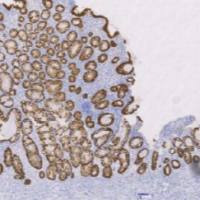

Product Image |

|